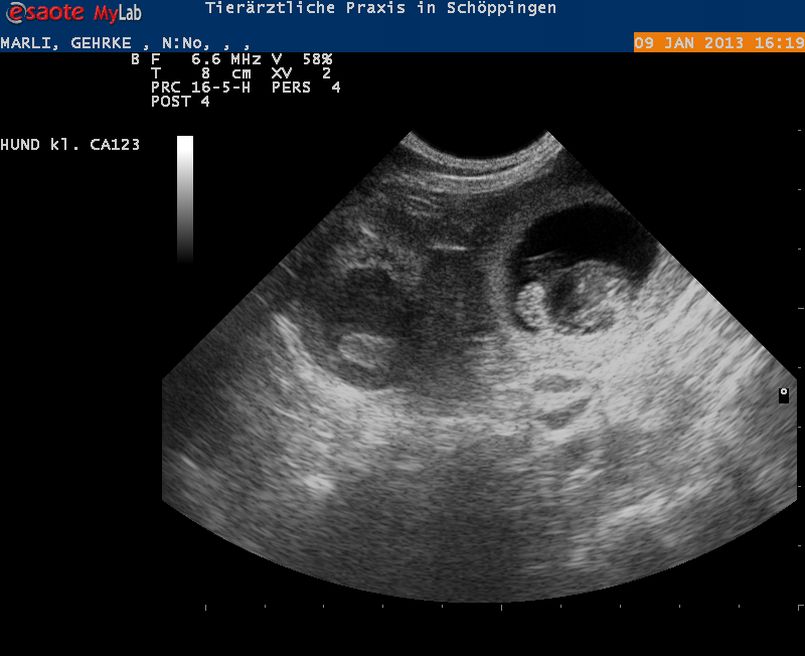

Donnerstag, 10. Januar 2013 - 11:32 Uhr

Wir erwarten Welpen, der Ultraschall hat es betätigt!!!

Mali und Bill erwarten Welpen, ich freu mich

Mali von Silverstone X Incredible Imp Nuo Bjaurybes